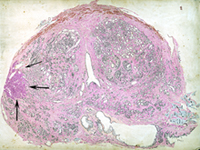

Los estudios en autopsias han demostrado la presencia de cáncer de próstata en uno de cada 3 varones examinados, pero el 80% de estos tumores tienen un tamaño muy pequeño y son clínicamente insignificantes. A los 70 años las autopsias muestran que un 46% de los varones tienen un cáncer de próstata, afortunadamente, en comparación con otros cánceres, tiene un crecimiento muy lento. Se calcula que un 90% de todos los cánceres de próstata permanecerán en estado latente durante décadas. En el 85-90%% de los hombres mayores de 80 años se encuentran focos microscópicos de adenocarcinoma. De este modo podemos decir que la mayor parte de los hombres con cáncer de próstata mueren por causas ajenas al tumor maligno.